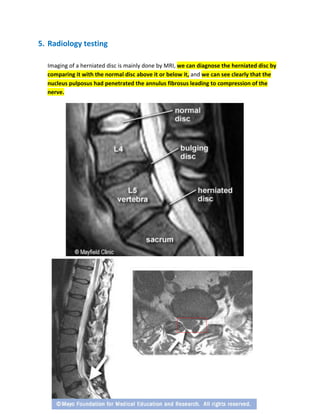

Imaging of a herniated disc is mainly done by MRI, we can diagnose the herniated disc by

comparing it with the normal disc above it or below it, and we can see clearly that the

nucleus pulposus had penetrated the annulus fibrosus leading to compression of the

nerve.